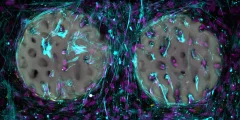

رقائق الأوعية الدموية عبارة عن أجهزة ميكروفلويديك مصممة لتكرار الأوعية الدموية البشرية على نطاق صغير جدًا. يمكن تصميمها خصيصًا للمرضى الأفراد وتقديم طريقة غير حيوانية لدراسة تدفق الدم وتقييم العلاجات المحتملة. عملت جينيفر لي، طالبة الماجستير في الهندسة الطبية الحيوية، في مختبر الدكتور أبهيشيك جاين لتصميم شريحة أوعية دموية متقدمة قادرة على إعادة إنتاج مجموعة واسعة من الأشكال التي يمكن رؤيتها في الأوعية الدموية الحقيقية.

يعتمد عمل لي على أبحاث سابقة في نفس المختبر. قبل بضع سنوات فقط، قام معلمها وطالب الدراسات العليا السابق الدكتور تانماي ماثور بتطوير تصميم مستقيم لشريحة الوعاء. تم تنفيذ كلا المشروعين في مختبر Bioinspired Translational Microsystems تحت إشراف Jain، وهو أستاذ مشارك وزميل كلية Barbara and Ralph Cox’53 في الهندسة الطبية الحيوية. تم نشر بحث لي في مختبر على شريحة وسيظهر على غلاف عدد مايو 2025 من المجلة.